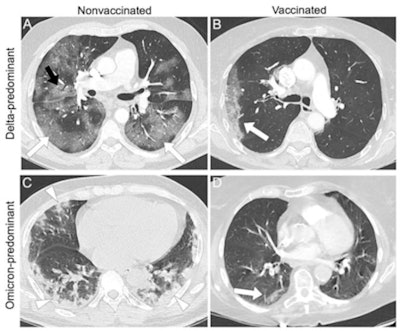

Representative examples of patients with different vaccine statuses during the delta-predominant and omicron-predominant periods. (A) Axial CT pulmonary angiogram (CTPA, with lung kernel) of a 65-year-old, nonvaccinated, male patient during the delta-predominant period showing typical CT for COVID-19, i.e., bilateral and asymmetric ground glass opacities (GGOs, white arrows) affecting the central and peripheral lung, associated with reticulations (black arrow) responsible for the 'crazy paving' aspect. The severity score assessed on the entire CTPA was 'severe' extent. (B) Axial CTPA in 57 years old vaccinated male patient (2 doses) during the delta-predominant period showing a "compatible" chest CT for COVID-19, i.e., single unilateral peripheral GGO (white arrow), with a "minimal" severity score. (C) Axial chest CT without contrast medium injection in a 69-year-old nonvaccinated male patient during the omicron predominant showing peripheral, bilateral, and asymmetric consolidations (white arrowhead), classified as 'compatible' with COVID-19. The severity score on the entire chest CT was "extended." (D) Axial CTPA in a 70-year-old vaccinated female patient (3 doses) showing a single small peripheral lesion combining GGO and consolidation (white arrow) classified as "indeterminate" with a "minimal" severity score. Images and caption courtesy of Radiology.The study results underscore the need for radiologists to track the "influence of vaccination and novel variants on CT findings and adapt their interpretations and conclusions accordingly, especially since full vaccination coverage is increasing and new omicron subvariants can reinfect previously immunized individuals," Crombe's team concluded.